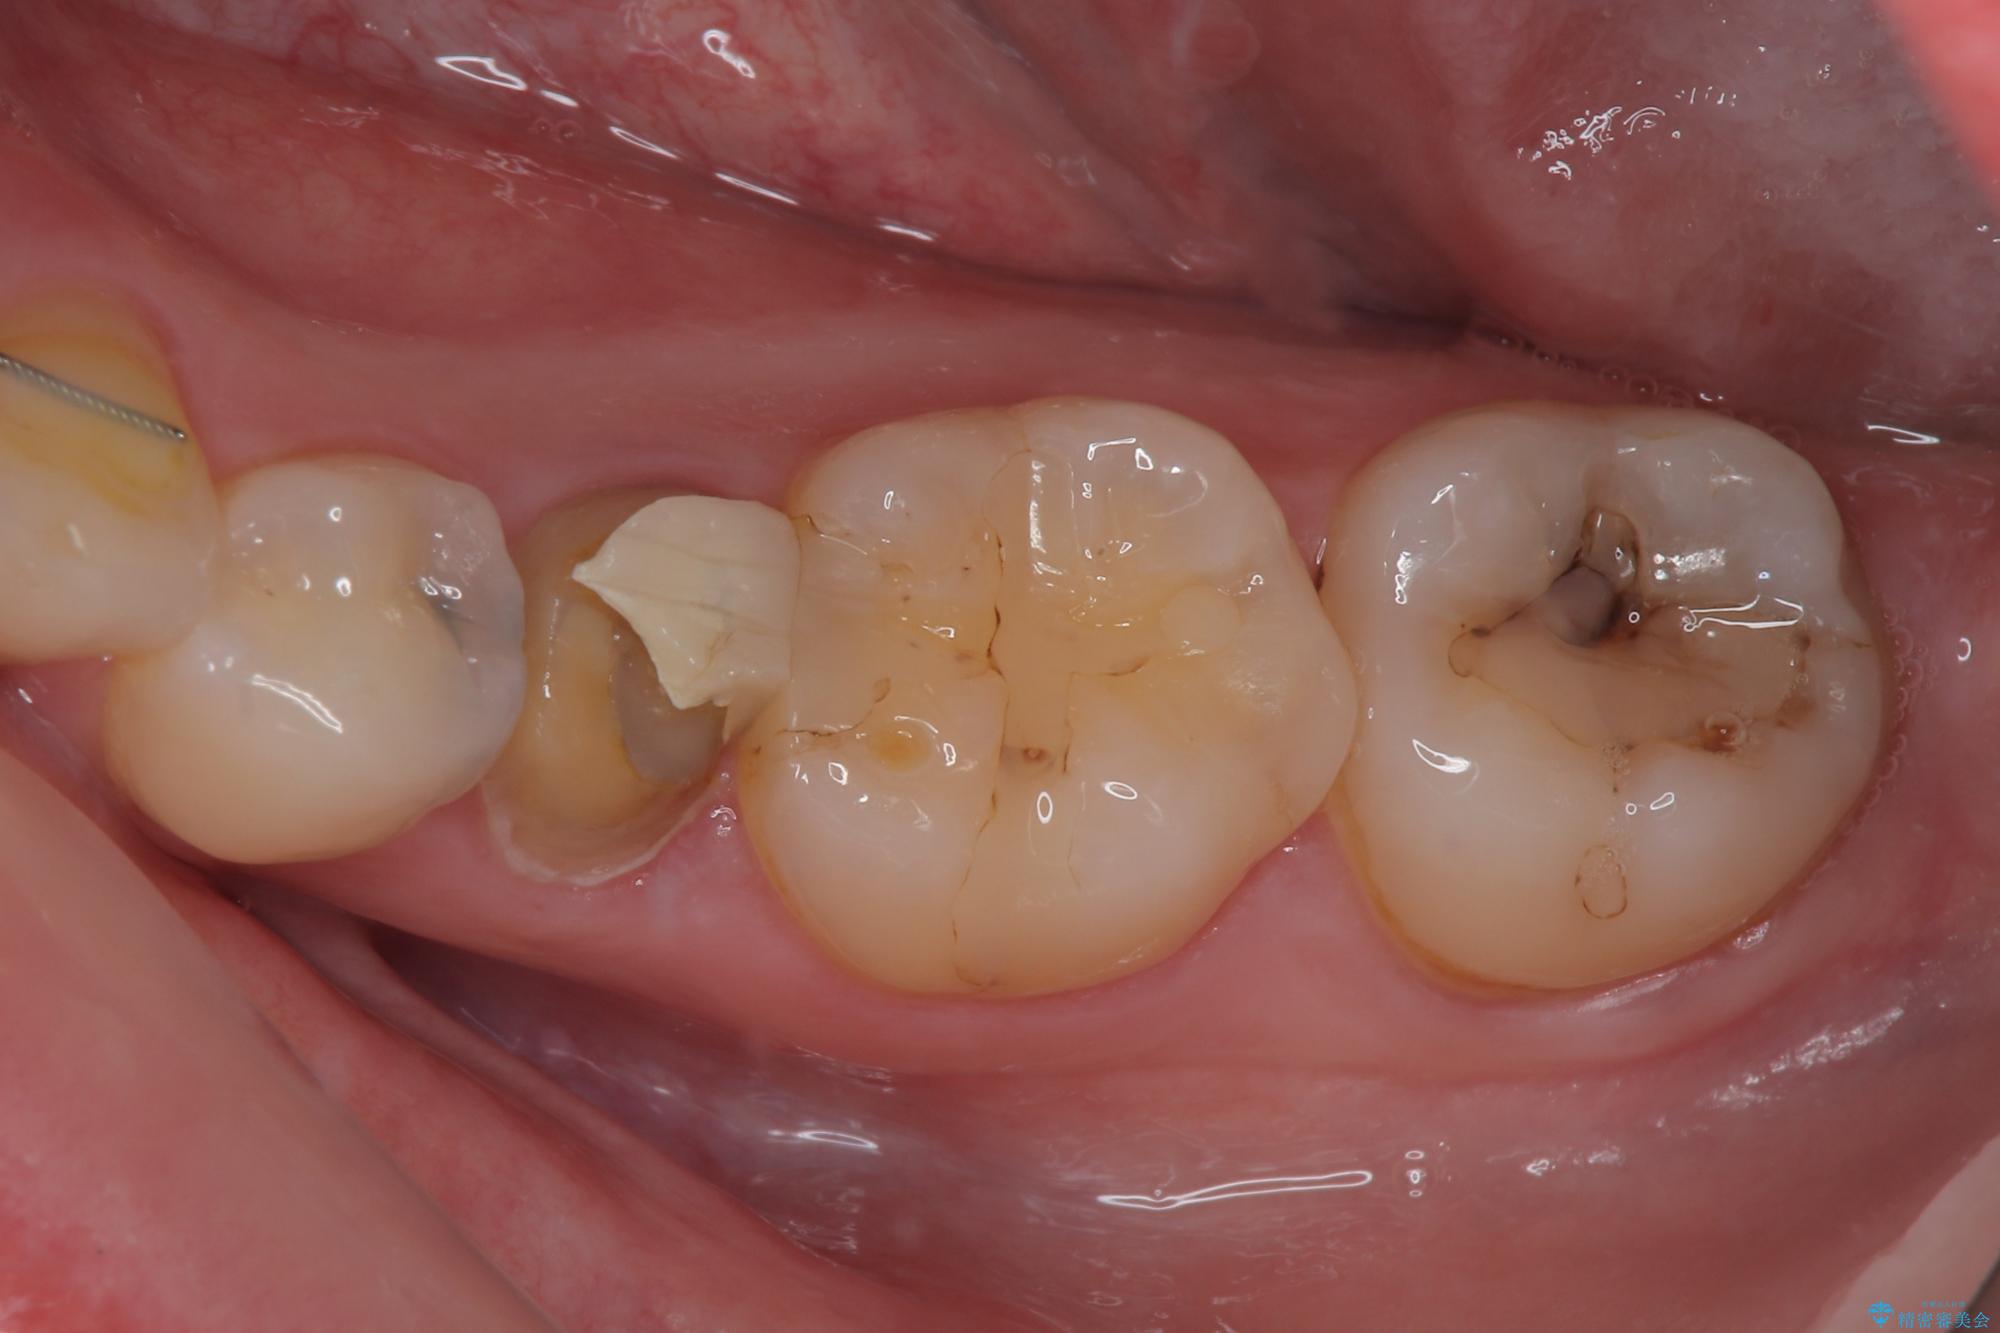

- 左下の被せものが割れたとのことで来院された患者様です。検査の結果、左下の前から4番目の歯はセラミックインレー修復、左下の5番目のところはオールセラミッククラウンによる補綴治療を行っていくことにしました。

拡大鏡視野下で被せもの、虫歯の除去を行い、オールセラミッククラウン、セラミックインレーに適した形に整えました。